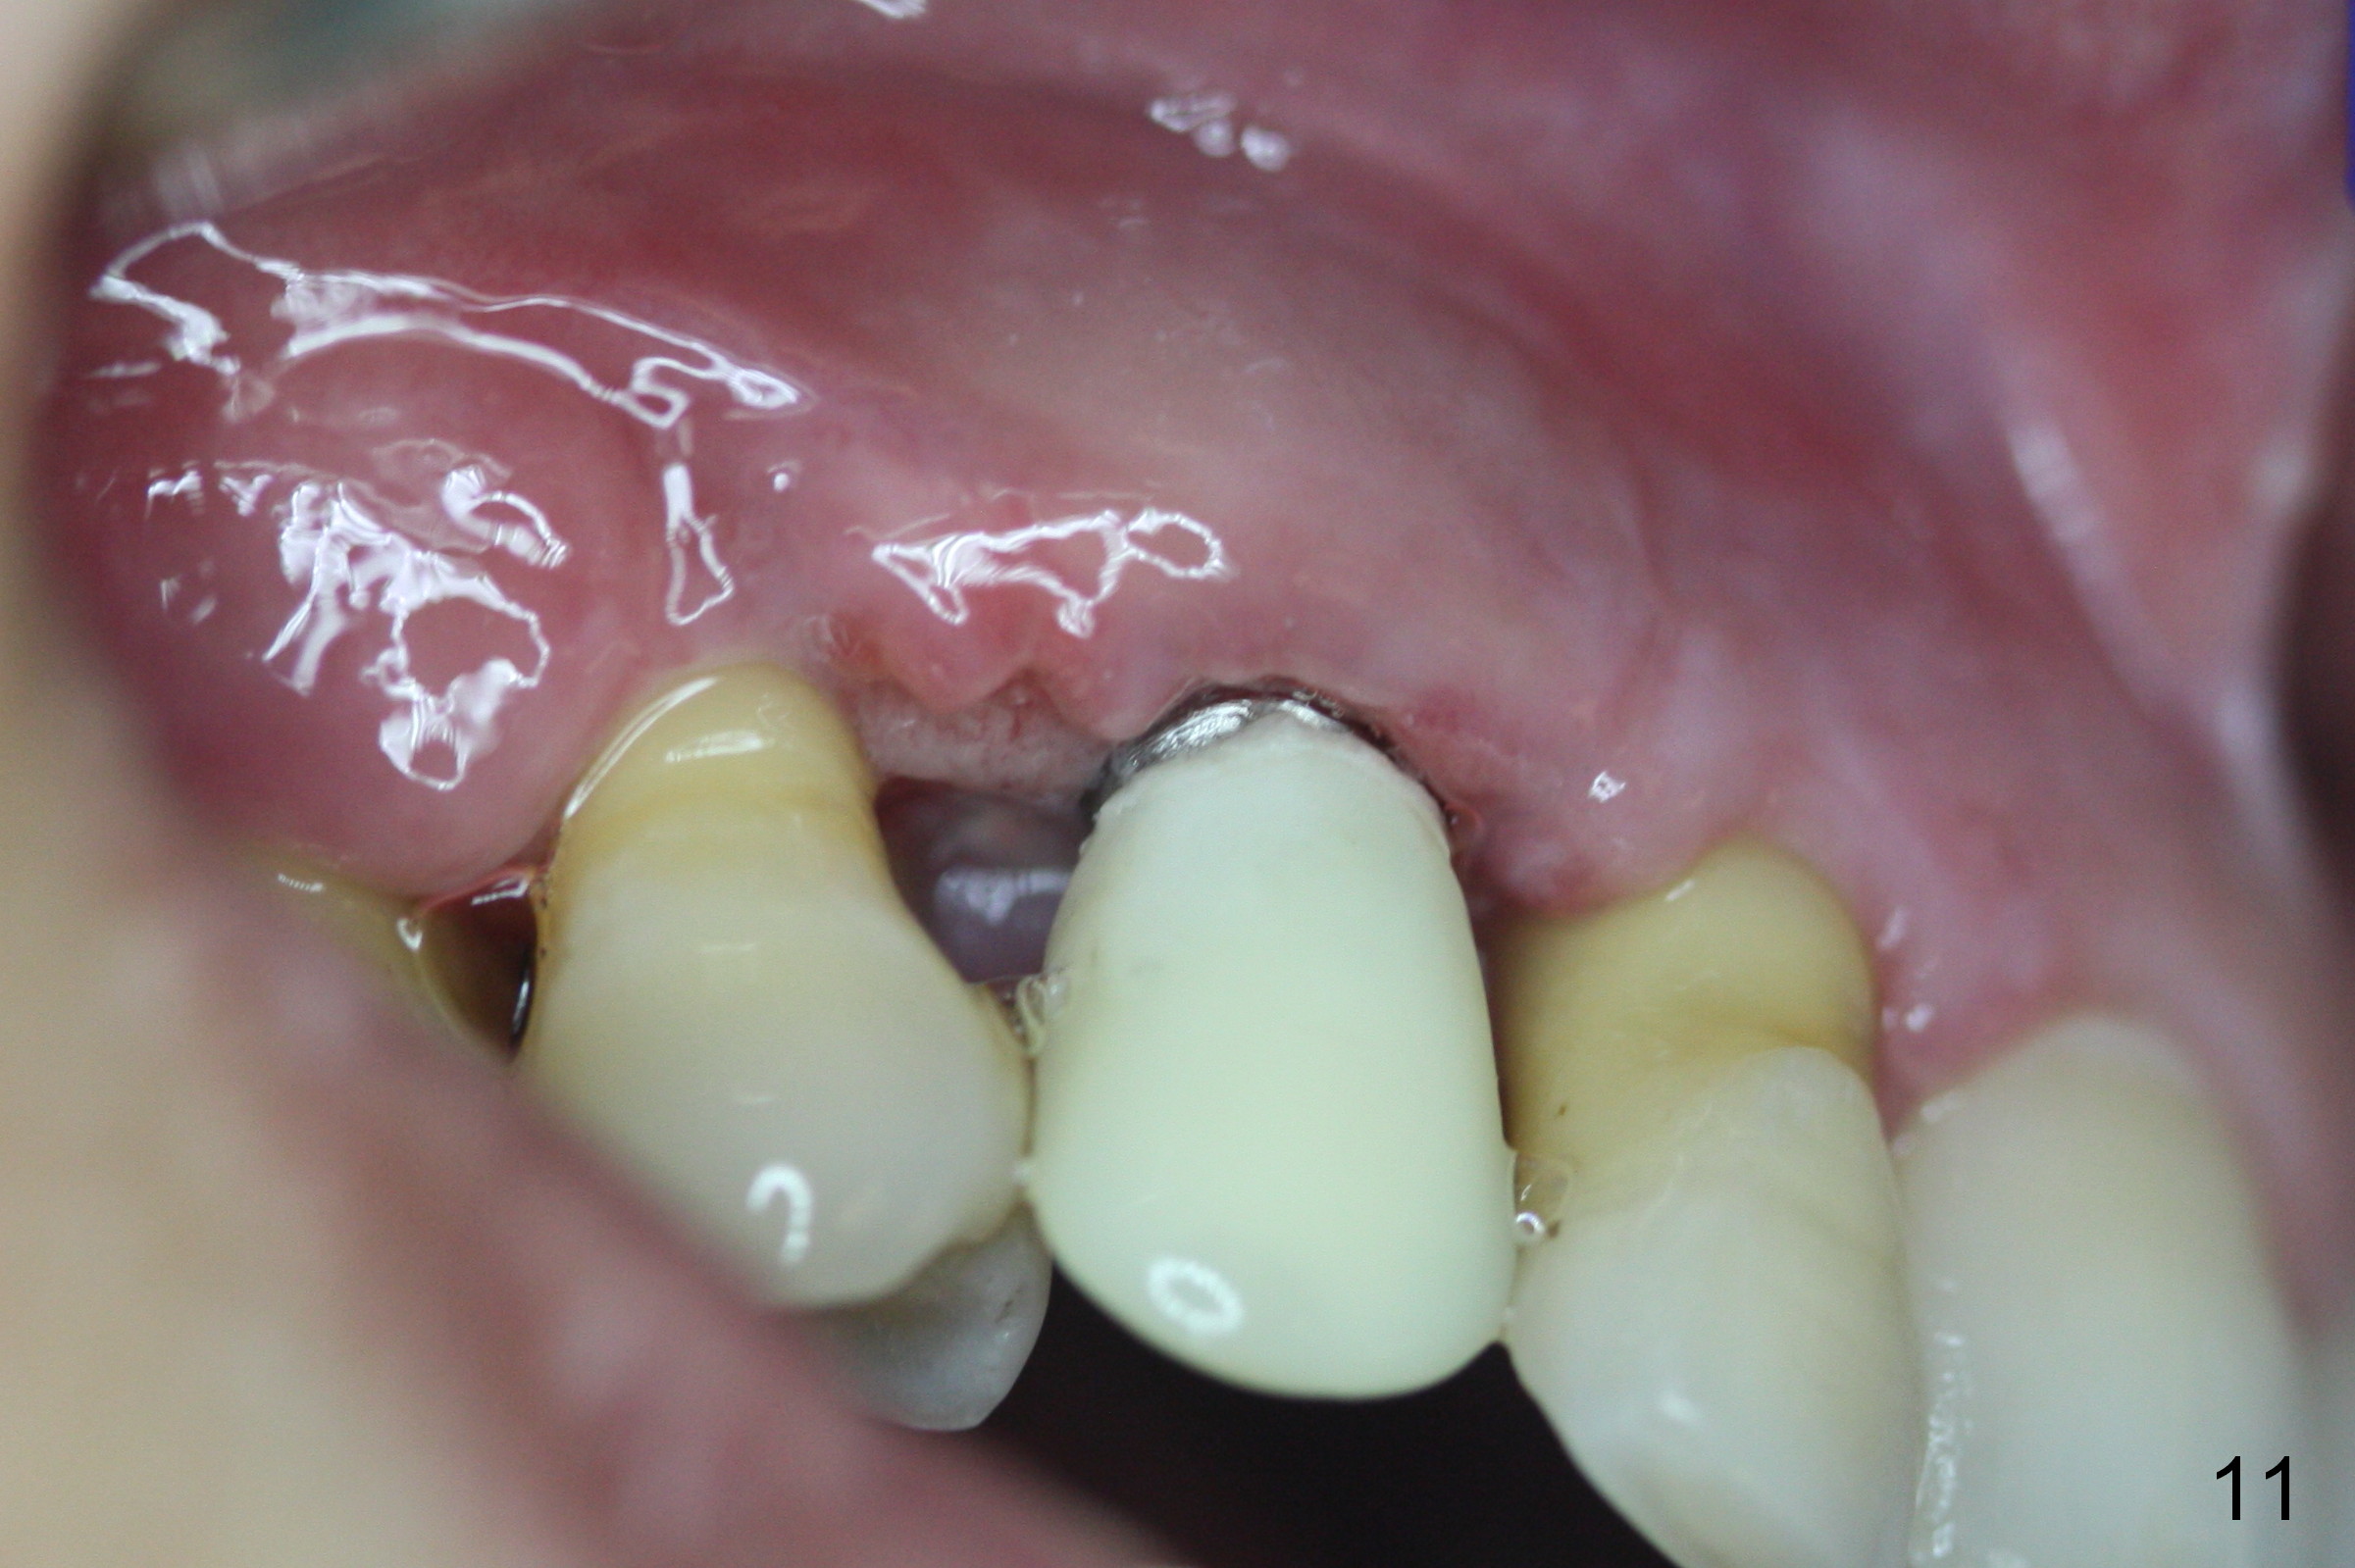

The patient complains of bad smell from the operative field 7 days postop. The wound is gapping with pseudo membrane, which is re-epithelized 14 days postop (Fig.11,12 *) with disappearance of the bad smell.